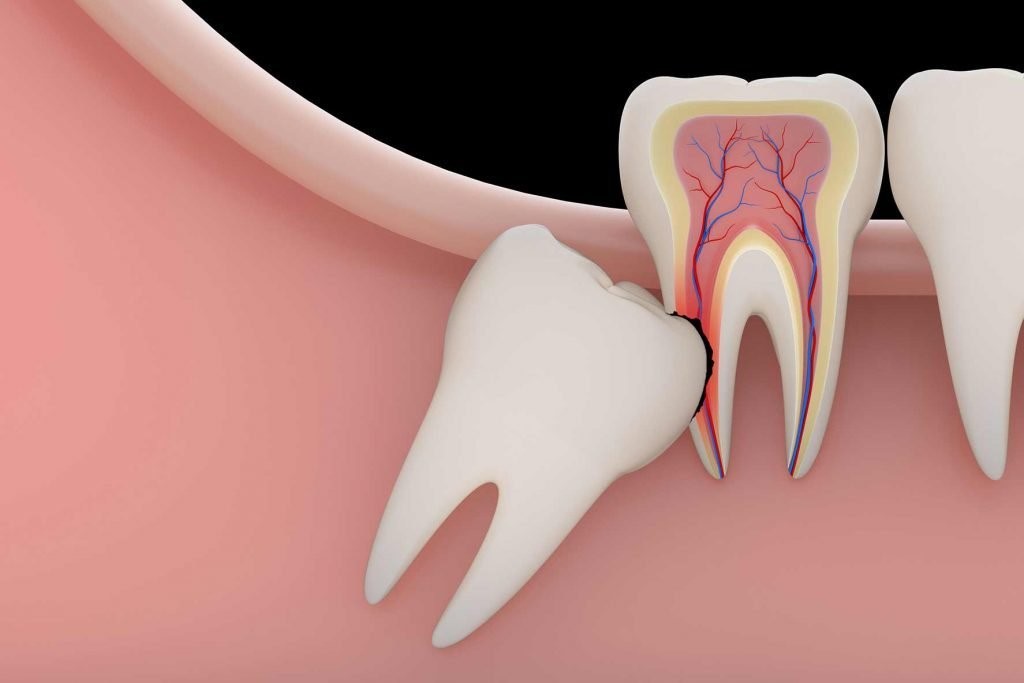

- Do răng mọc chen chúc: vì răng khôn mọc rất muộn và mọc khi những chiếc răng khác của cung hàm đã lấp đầy gần như tất cả khoảng trống của toàn hàm nên răng khôn thường không có đủ khoảng trống để mọc thẳng. Thay vào đó, chúng hay mọc xiên, mọc lệch, mọc chen chúc vào những chiếc răng kế bên. Một số trường hợp đặc biệt răng khôn không thể mọc lên được và bị mắc kẹt tại nướu khiến người bệnh luôn cảm thấy đau buốt.